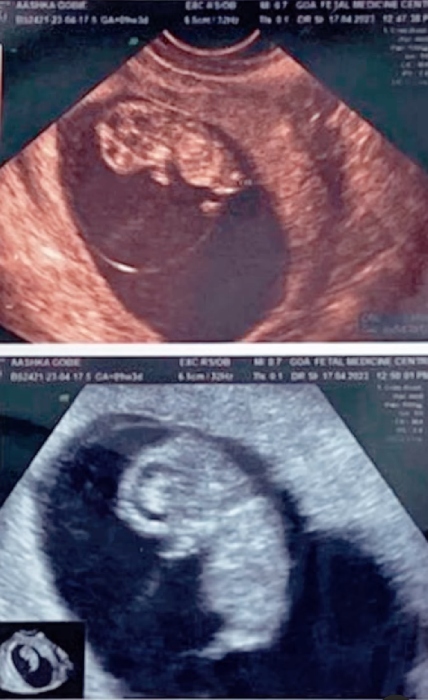

Aashka Goradia is pregnant with her first child. Aashka and her husband Brent Globe married on December 1, 2017, in Goa. After six years of 'happily ever after' and exploring the world together, Aashka and Brent are all set for nesting. Recently, the mommy-to-be, Aashka Goradia shared glimpses of her first sonography and also shared her experience of seeing her first child, nurturing in her womb.

On May 23, 2023, Aashka took to her Instagram handle and posted a cutesy video compilation of her beautiful pregnancy moments. The clip started with the parents-to-be, Aashka and Brent's picture as they enjoyed their time on a cruise. Followed by first glimpses of Aashka's pregnancy scan. In one of the pictures, Aashka flaunted her baby bump in a black dress.

Alongside it, the mommy-to-be Aashka expressed her happiness on seeing her child nurturing and growing inside her womb. She called it magical, and her note can be read as:

"So thankful it was magical to see this one for the first time It reminded me of all the beautiful days together with @ibrentgoble. Each day is magical. Filled with joy, excitement and fears but the anticipation to see this little one covers all fears. Dear husband - we have grown, everything is more special. To all the parents, including mine - thank you! It’s truly the greatest ride!"